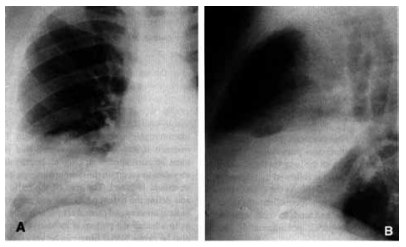

Paciente de 22 anos, sem comorbidades, apresenta quadro de febre, tosse e dor torácica há 2 dias. O r-X é apresentado a seguir. A ausculta pulmonar mostra estertores crepitantes na base direita e saturação de 92% em ar ambiente.

Nesse momento, a conduta adequada é: